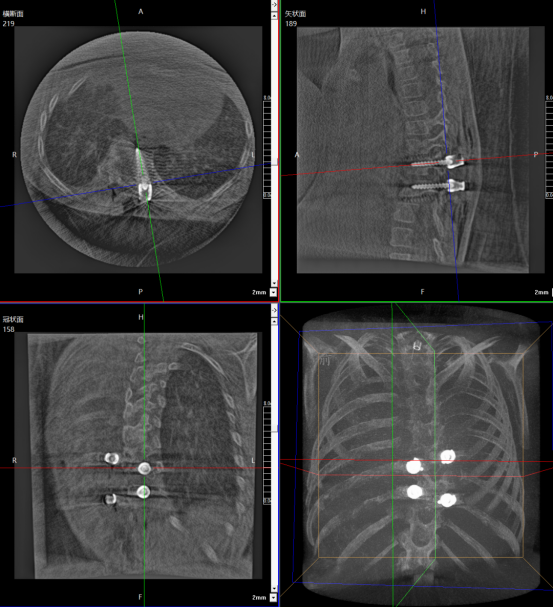

Patient: Female, 5 years old

Clinical Symptoms: Asymmetrical back, uneven shoulders, scoliosis

Surgical Indication: Congenital hemivertebra deformity accompanied by scoliosis, which affects normal growth and development. Surgical correction was necessary. Early surgical intervention can effectively prevent deformity progression and improve prognosis.

Surgical Approach: Posterior hemivertebrectomy combined with short-segment fixation and fusion

Surgical Goals: Eliminate the deforming element, correct spinal deformity, restore spinal balance, and preserve the patient's growth potential.

One-time planning for quadruple K-wire insertion

The robotic arm enhanced stabilization of surgical instruments, enabling precise execution. Guided by pre-planned trajectories, the system achieved accurate single-attempt pedicle screw placement within narrow vertebral pedicles - effectively navigating the 'anatomical labyrinth'. This approach eliminated risks associated with repeated positioning attempts. The fully integrated system demonstrated perfect coordination, successfully completing the implantation of four pedicle screws with sub-millimeter accuracy.

Fluoro-verified precise K-wire insertion

Fluoro-verified precise screw implantation